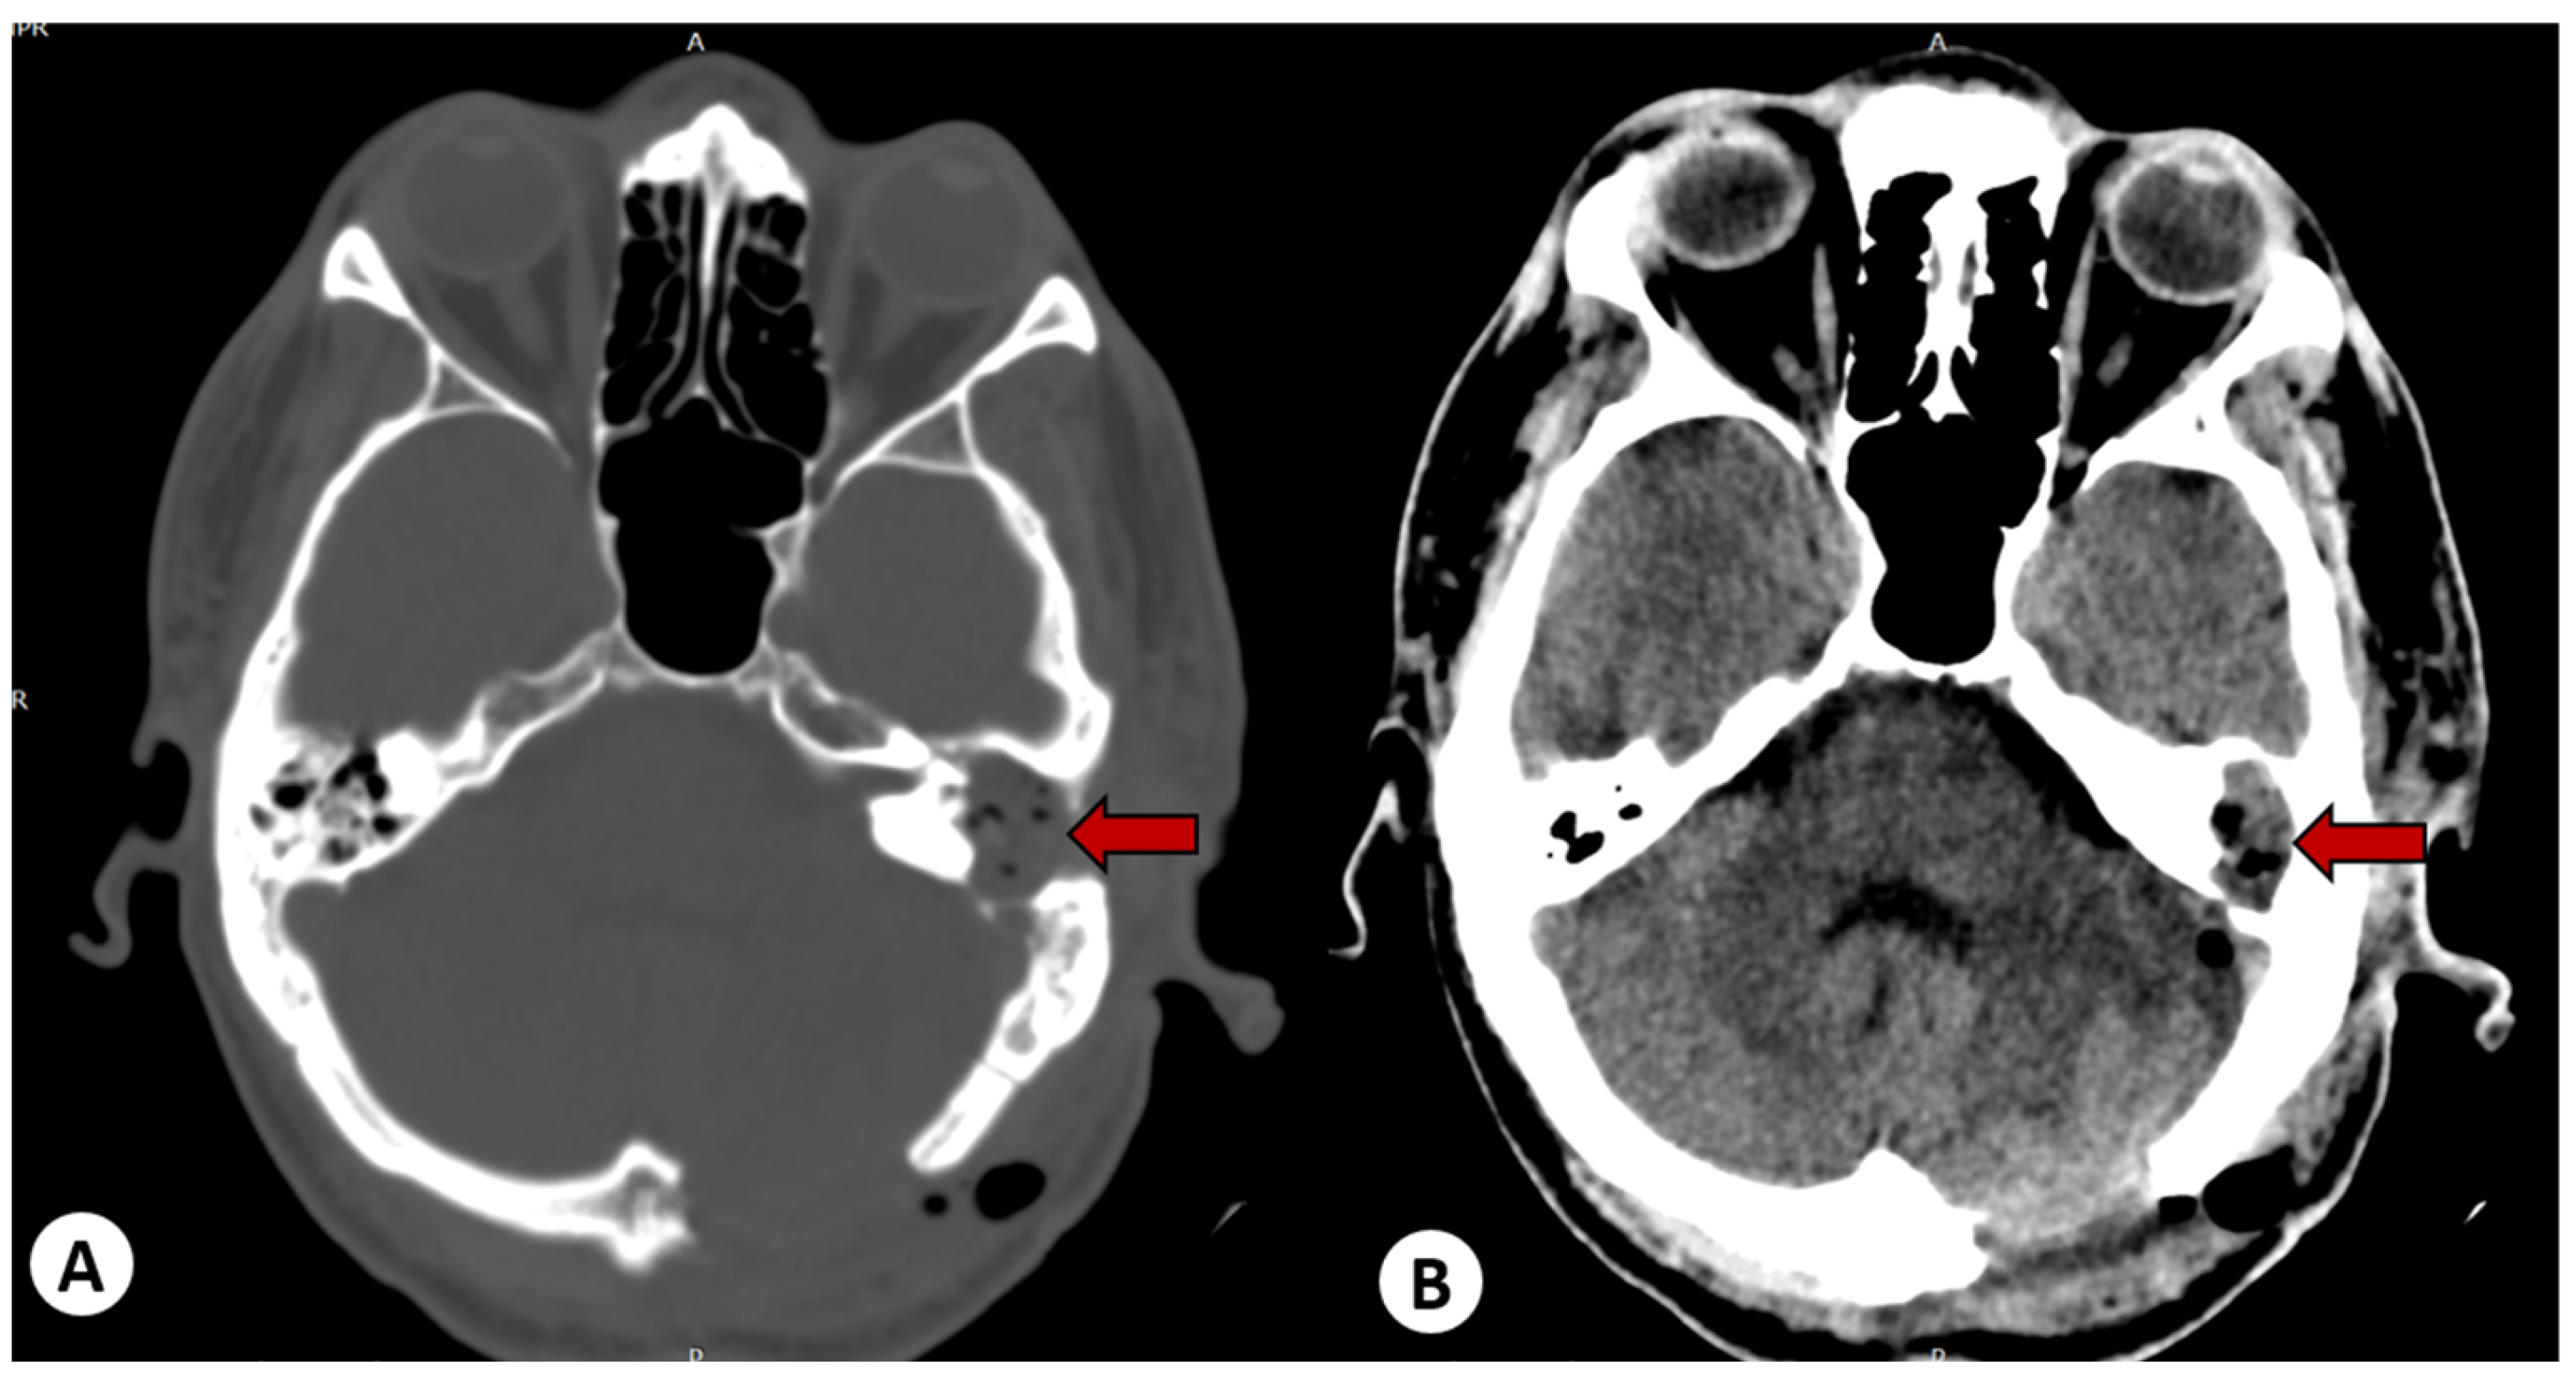

2.2.2. Imaging Studies

3.5. Imaging Studies